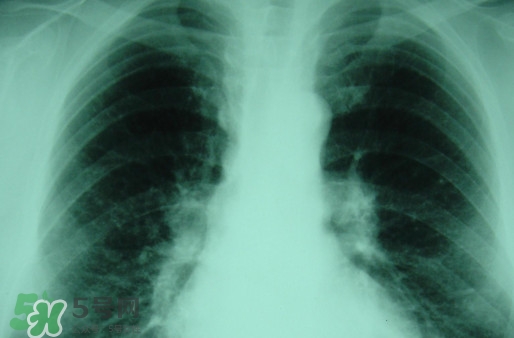

塵肺病多半是肺部灰塵太多導(dǎo)致肺部承載大清理工作降低導(dǎo)致的,對此有人提出換肺治療的方法。那么,塵肺病能換肺治愈嗎?塵肺病不能吃什么?

塵肺病能換肺治愈嗎

塵肺病換肺理論上可行,實(shí)際中也可以操作,但那是有錢人的游戲

目前換肺治療塵肺病是有的,但壽命啥的都會有影響

而且你要找到適合的供體也很難。